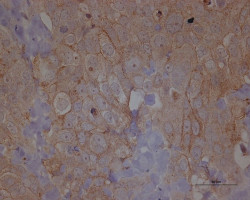

Consiguen un nuevo avance para ayudar al sistema inmunitario en la lucha contra el cáncer

Una nueva investigación ha identificado un posible tratamiento que podría mejorar la capacidad del sistema inmunitario humano para buscar y destruir las células cancerosas del organismo. Los científicos han identificado una forma de restringir la actividad de un grupo de células que regulan el sistema inmunitario, lo que a su vez puede desencadenar que otras células inmunitarias ataquen los tumores en los pacientes con cáncer.